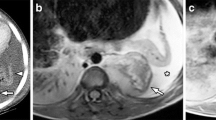

Sagittal short tau inversion recovery (STIR) (a) and T1-weighted (b) images of the vertebral column in a 1.5-year-old boy with Langerhans cell histiocytosis (LCH), illustrating the typical vertebral plana at the level of Th12 (white arrow) as well as involvement of vertebral body L4 and S2 (white arrowheads). Furthermore, a heterogeneous enlarged thymus is present (open white arrow), suspicious of LCH involvement. Coronal 3D T2-weighted turbo spin-echo (T2-TSE) image (c) acquired to demonstrate/rule out intrathoracic and intra-abdominal organ involvement, once again showing the thymic involvement in LCH (white arrow). Coronal short tau inversion recovery (STIR) (d) and contrast-enhanced T1-weighted (e) images of the skull, showing two LCH lesions in the skull with epidural extension (white arrows)